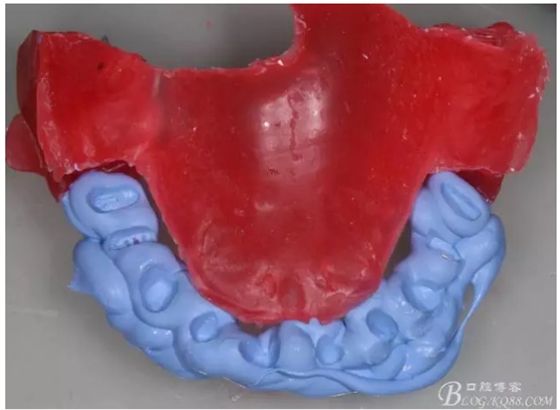

牙體預(yù)備前先咬蠟記錄,記錄患者的垂直高度,在預(yù)備后再把蠟記錄放入口內(nèi),用咬合記錄硅橡膠再記錄牙體預(yù)備后的咬合記錄

這樣就準(zhǔn)確的記錄和還原了原來(lái)的垂直高度,更多垂直距離的確定在8月3日kq88課堂上還有提及歡迎大家來(lái)聽(tīng)課啊,